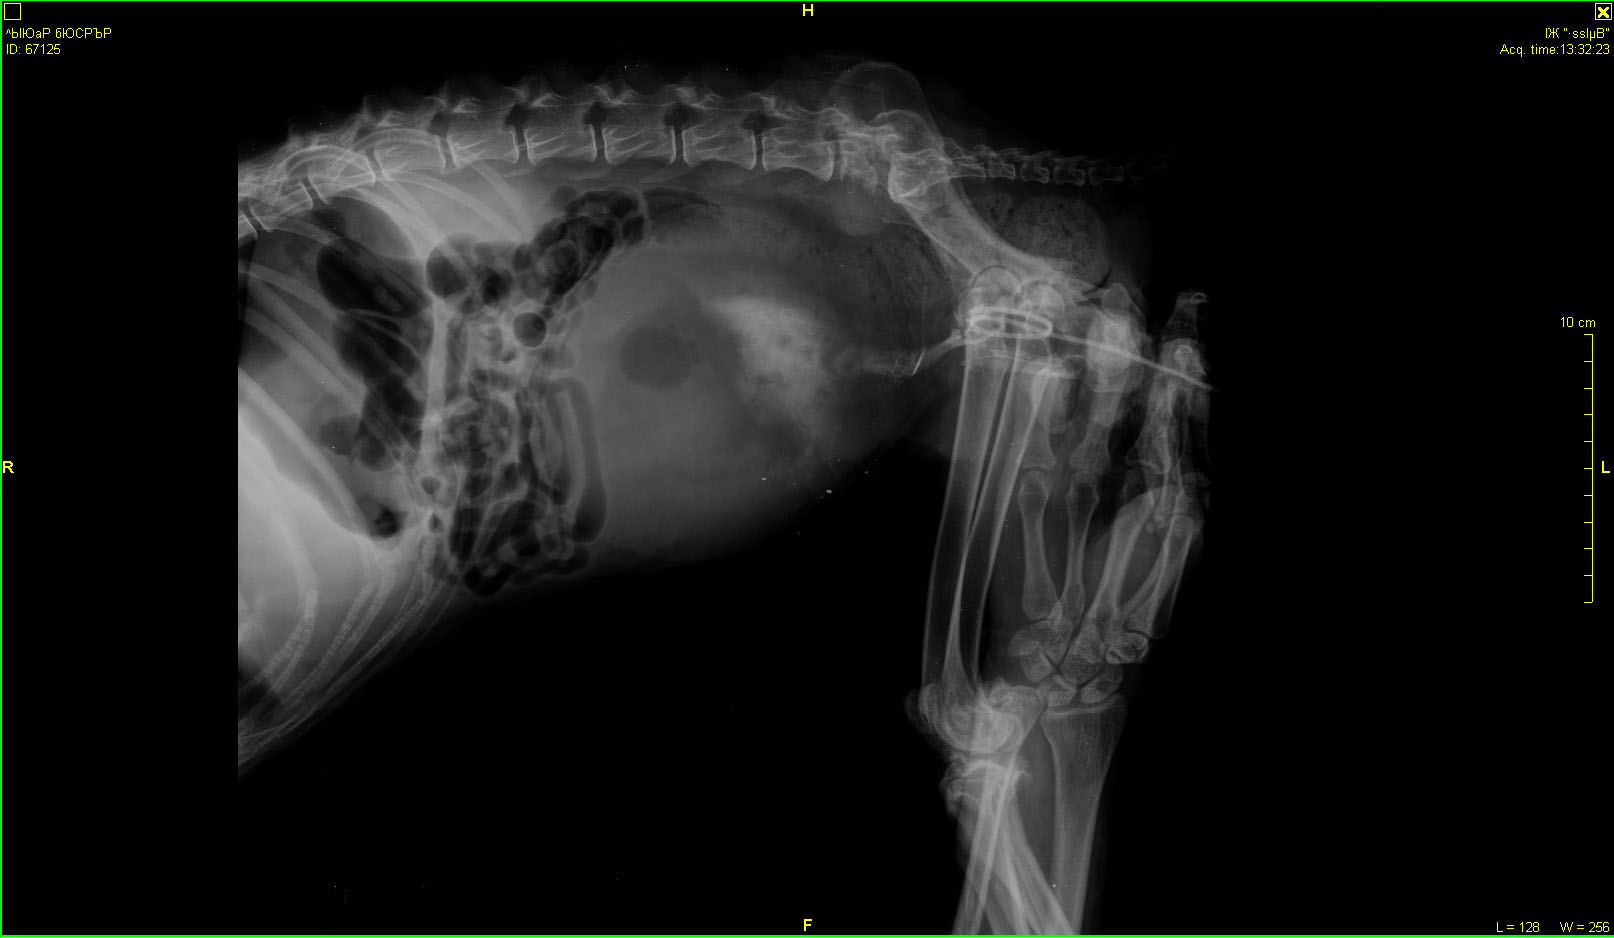

Рентген в Зоовете. Может, кто разбирается, что скажет?

"Вкратце. Новообразования в мочевом пузыре и в позвоночнике, раздробился позвонок, про который думали, что перелом. Был уж там перелом раньше или нет, сейчас уже не важно. Проблемы с мочевым - сам не мочится, только когда переполняется, но переполняться нельзя. Спасаемся катетером. Ну и плюс, конечно, повреждения спинного мозга, сильная обезвоженость, интоксикация, я всего не запомнила, Галина Юрьевна больше во всём разбирается, я выложу сейчас результаты анализов. Капельницы по 4 часа 2 раза в день, сейчас капается. Врач ставит онкологию, скорее всего злокачественную, это не достоверно, но скорее всего. Операцию смысла делать нет, потому что в её состоянии она не выдержит. Предложил или усыпить сразу, или капать и смотреть дальше по состоянию. Он не уверен, что она проживёт и более 5 дней. Хотя вот вчера и сегодня утром чуть курочки поела, сейчас ещё попробую дать. Но слабая конечно. Постоянно пьёт. Сейчас всё сосканирую и выложу.

Хотим показать результаты обследований Гаранину. Может быть, если состояние улучшиться, рискнём на операцию. Или во Владимире Ильину. "

Аня, прошу прощения за совет, но Вы не хотите показать рентген человеческим врачам-онкологам? Скажем у нас в онкодиспанцере. Когда я обращалась с ногой своей собаки (правда это было давно) именно там на основании рентгена мне определили, что нет онкологии, а есть разрушение кости вызванное остеомелитом. И второе - локализация опухоли мочевого пузыря по УЗИ определялась?